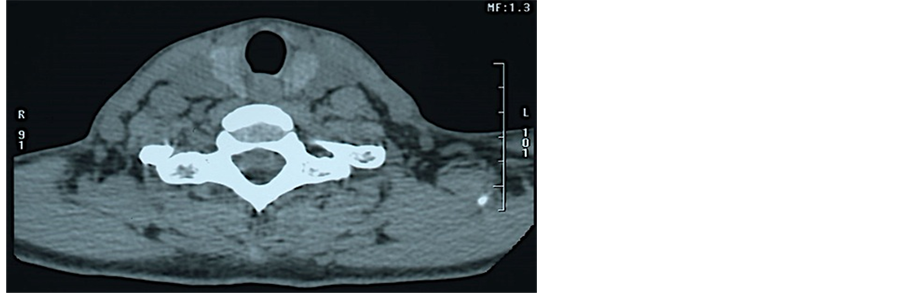

A 52-year-old female presented with the chief complaint of pain associated with swelling apical to tooth #12 (the left maxillary first premolar). Radiographic findings showed a diffuse, radiolucent lesion with loss of the lamina dura around tooth #12 (Figure 1). First, to start the root canal treatment, we removed the full metal crown and metal core post. Then, we removed the gutta-percha point in the root canal using a K file. After length calculation, using Root ZX (Morita, Japan), we used RC-Prep (Hakusui, Japan) for root canal enlargement to the size of #80. The canal was irrigated with 5% sodium hypochlorite (Antiformin, Wako), following 3% EDTA solution (Smear Clean, Nishika, Japan) and normal saline solution in 5-mL syringes with no. 25-G blunt-end needles. As irrigation with sodium hypochlorite began on the buccal canal, the patient reacted violently, reporting that she had a very sharp pain and her face felt as though it was being blown up like a balloon. A noticeable swelling on the left side of her face was observed: the area extended laterally to the nose, reaching about 2 cm below the lower eyelid and below the lower lip and posterior to it. The peak of the swelling was at the center of an imaginary line drawn from the corner of the mouth to the tip of the ear (Figure 2(a), Figure 2(b)). Irrigation was stopped, and the tooth was dried with vacuum suction, and finally with paper points. The tooth was left open (Figure 2(c)). A conventional computed tomography (CT) scan is shown in Figure 3. Around the left cheek, diffuse signals were observed between the soft tissues of the lower jaw from the lower edge (Figure 3(a)). Shadow image spots showing low absorption were observed, so contamination with air (gas) was suspected in the soft tissue inside (Figure 3(b)). In the dental CT, X-ray transmission images could be seen around the root apex of the maxillary left canine; the left nasal bone and the low cortical bone adjacent to it had been partially absorbed. There was no narrowing of the pharyngeal cavity, nor deformation of the lateral pharyngeal wall or displacement (Figure 3(c)). Cefcapene 300 mg per day for 7 days and 21 tablets of 60-mg loxonin, as an analgesic, were prescribed, and the patient was asked to return the next day. At 20 h after the episode, she was seen again; she said that the sharp pain had continued for the rest of the day, but the swelling seemed to have subsided. An examination showed that the swelling was focused on the upper face. No fluctuation was felt inside the mouth or on palpating the face. Neither ecchymosis nor closure of the eye was noted (Figure 4(a)). The sinus tract was closed (Figure 4(d)). On the sixth days, the swelling had subsided further, and moved to the lower jaw (Figure 4(b)). The pain had largely resolved. On day 11, the pain had ended completely. Slight swelling of the face and the lower jaw remained (Figure 4(c)). Root canal therapy was continued, using only saline irrigation, followed by filling with calcium hydroxide preparation, and the tooth was fitted with a temporary crown (Figure 4(e)). The postoperative sequence was uneventful, and 1 month later, the final obturation was performed with mineral trioxide aggregate (MTA, Dentsply, USA), in which the root apex was opened wide. The postoperative X-ray revealed an overextension of the MTA, extruding from both roots (Figure 5).

Figure 3. Computed tomography scan showed extensive gas in the soft tissue of the left cheek around the first premolar (axial view) (a); Arrow indicates the gas region. Panoramic view through the posterior. Arrow indicates the radiolucency at the apex of left maxillary premolar (b); Axial view of the pharyngeal region (c).

The cause of the subcutaneous emphysema was considered to be chlorine gas, generated by a chemical reaction between sodium hypochlorite and RC-Prep and washing out the sodium hypochlorite to the outside of the root apex. Sodium hypochlorite is toxic to vital tissues [10] -[13] . It is believed that in this case, by using sodium hypochlorite in a syringe, an inflammatory response was caused in the tissue. In addition, it is thought that because RC-Prep was present, the harm caused by the action of the sodium hypochlorite was enhanced. The reason for the CT scan was to examine how widespread the emphysema was, from the cervicofacial space, including the buccal, masticator, submandibular, parapharyngeal, and retropharyngeal spaces, to the mediastinum and precordium.